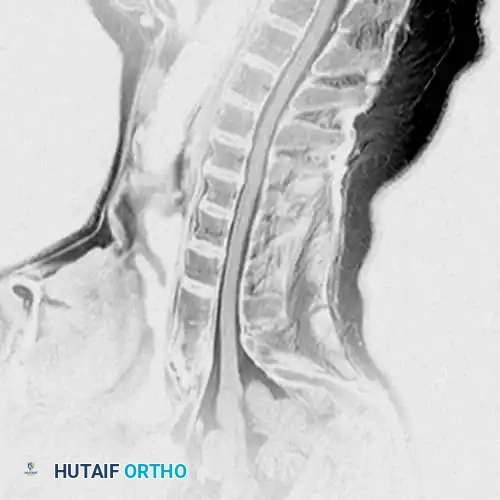

DIAGNOSTIC STUDIES Surgical Diagram

Fig. 39-6 A: MRI Sagittal view of a 45-year-old patient with right C7 radiculopathy. The MRI was inconclusive for a definitive disc herniation.